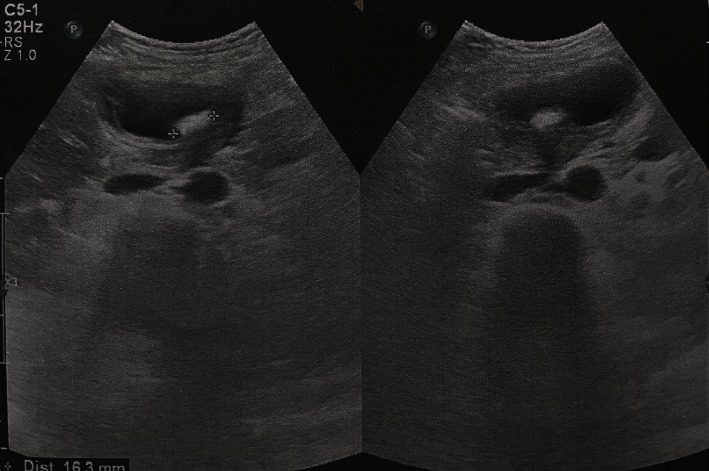

背景:胆囊肿胀是指胆囊沿胆囊管和胆囊动脉的轴线在其系膜上旋转。许多因素被认为是导致胆囊肿胀的原因,如解剖、机械、生理和荷尔蒙风险因素,但存在膨胀的胆囊和多余的系膜被认为是一个重要原因。病例介绍:一名 68 岁的妇女因右下腹疼痛和呕吐就诊,疼痛和呕吐已持续 2 天,并向肩胛间区域放射,还伴有恶心和呕吐。患者无黄疸,腹部检查显示右上腹触诊时有严重压痛并伴有戒备,但未触及肿块。白细胞升高,肝酶、胆红素和碱性磷酸酶正常。超声波检查显示有一块胆石,石壁厚度增加。服用抗生素和镇痛药后,临床症状没有明显改善。腹腔镜检查时发现胆囊肿胀,导致胆囊坏疽。患者接受了腹腔镜胆囊切除术。患者在术后第三天出院,病情明显好转,没有出现术后并发症。结论胆囊内翻是一种急性外科急症,通常见于老年人群。需要高度怀疑,尤其是在没有胆结石的情况下,并且必须与结石性胆囊炎相鉴别。大多数病例都是在手术中发现的。必须立即进行剥离和胆囊切除术,经过适当的手术干预后,大多数病例的预后都很好。

Background: Volvulus of gallbladder is defined as a rotation of the gallbladder on its mesentery along the axis of the cystic duct and cystic artery. Many factors are postulated to be the causes such as anatomical, mechanical, physiological, and hormonal risk factors but the presence of a distended gallbladder with a redundant mesentery is thought to be an important cause. Case presentation: A 68-year-old woman presented with right hypochondrial pain and vomiting for 2 days that was radiated to the interscapular region and associated with nausea and vomiting. The patient had no jaundice and the abdominal examination showed severe tenderness with guarding during palpation of the right upper abdomen with no palpable mass. The WBCs were elevated, with normal liver enzymes, bilirubin, and alkaline phosphatase. The ultrasound showed a single gallstone with increased wall thickness. There was no significant clinical improvement with antibiotics and analgesics. During laparoscopy, volvulus of the gallbladder was discovered causing gangrene of the gallbladder. Laparoscopic detorsion and successful laparoscopic cholecystectomy were performed. The patient was discharged on the third postoperative day with dramatic improvement with no postoperative complications. Conclusion: Gall bladder volvulus is an acute surgical emergency that is usually seen in the elderly population. It required a high index of suspicion especially in the absence of gallstones and must be differentiated from acalculous cholecystitis. Most cases are discovered at surgery. It must be managed with immediate detorsion and cholecystectomy, and the prognosis is excellent in most cases after an appropriate surgical intervention.